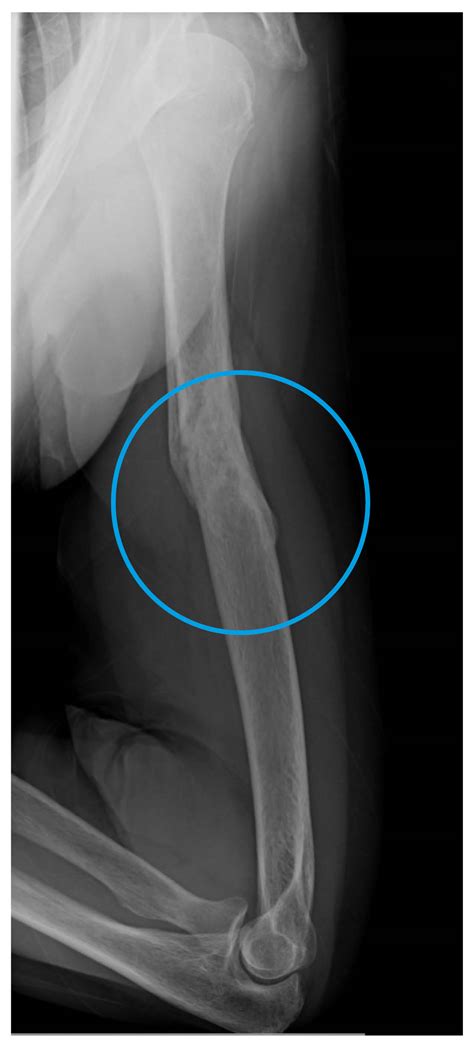

Understanding a Broken Humerus

A broken humerus can occur due to various reasons, including falls, sports injuries, or accidents. The humerus is divided into three parts: the proximal humerus (near the shoulder), the shaft of the humerus (the long middle section), and the distal humerus (near the elbow). The type and location of the fracture will determine the severity of the injury and the appropriate treatment.